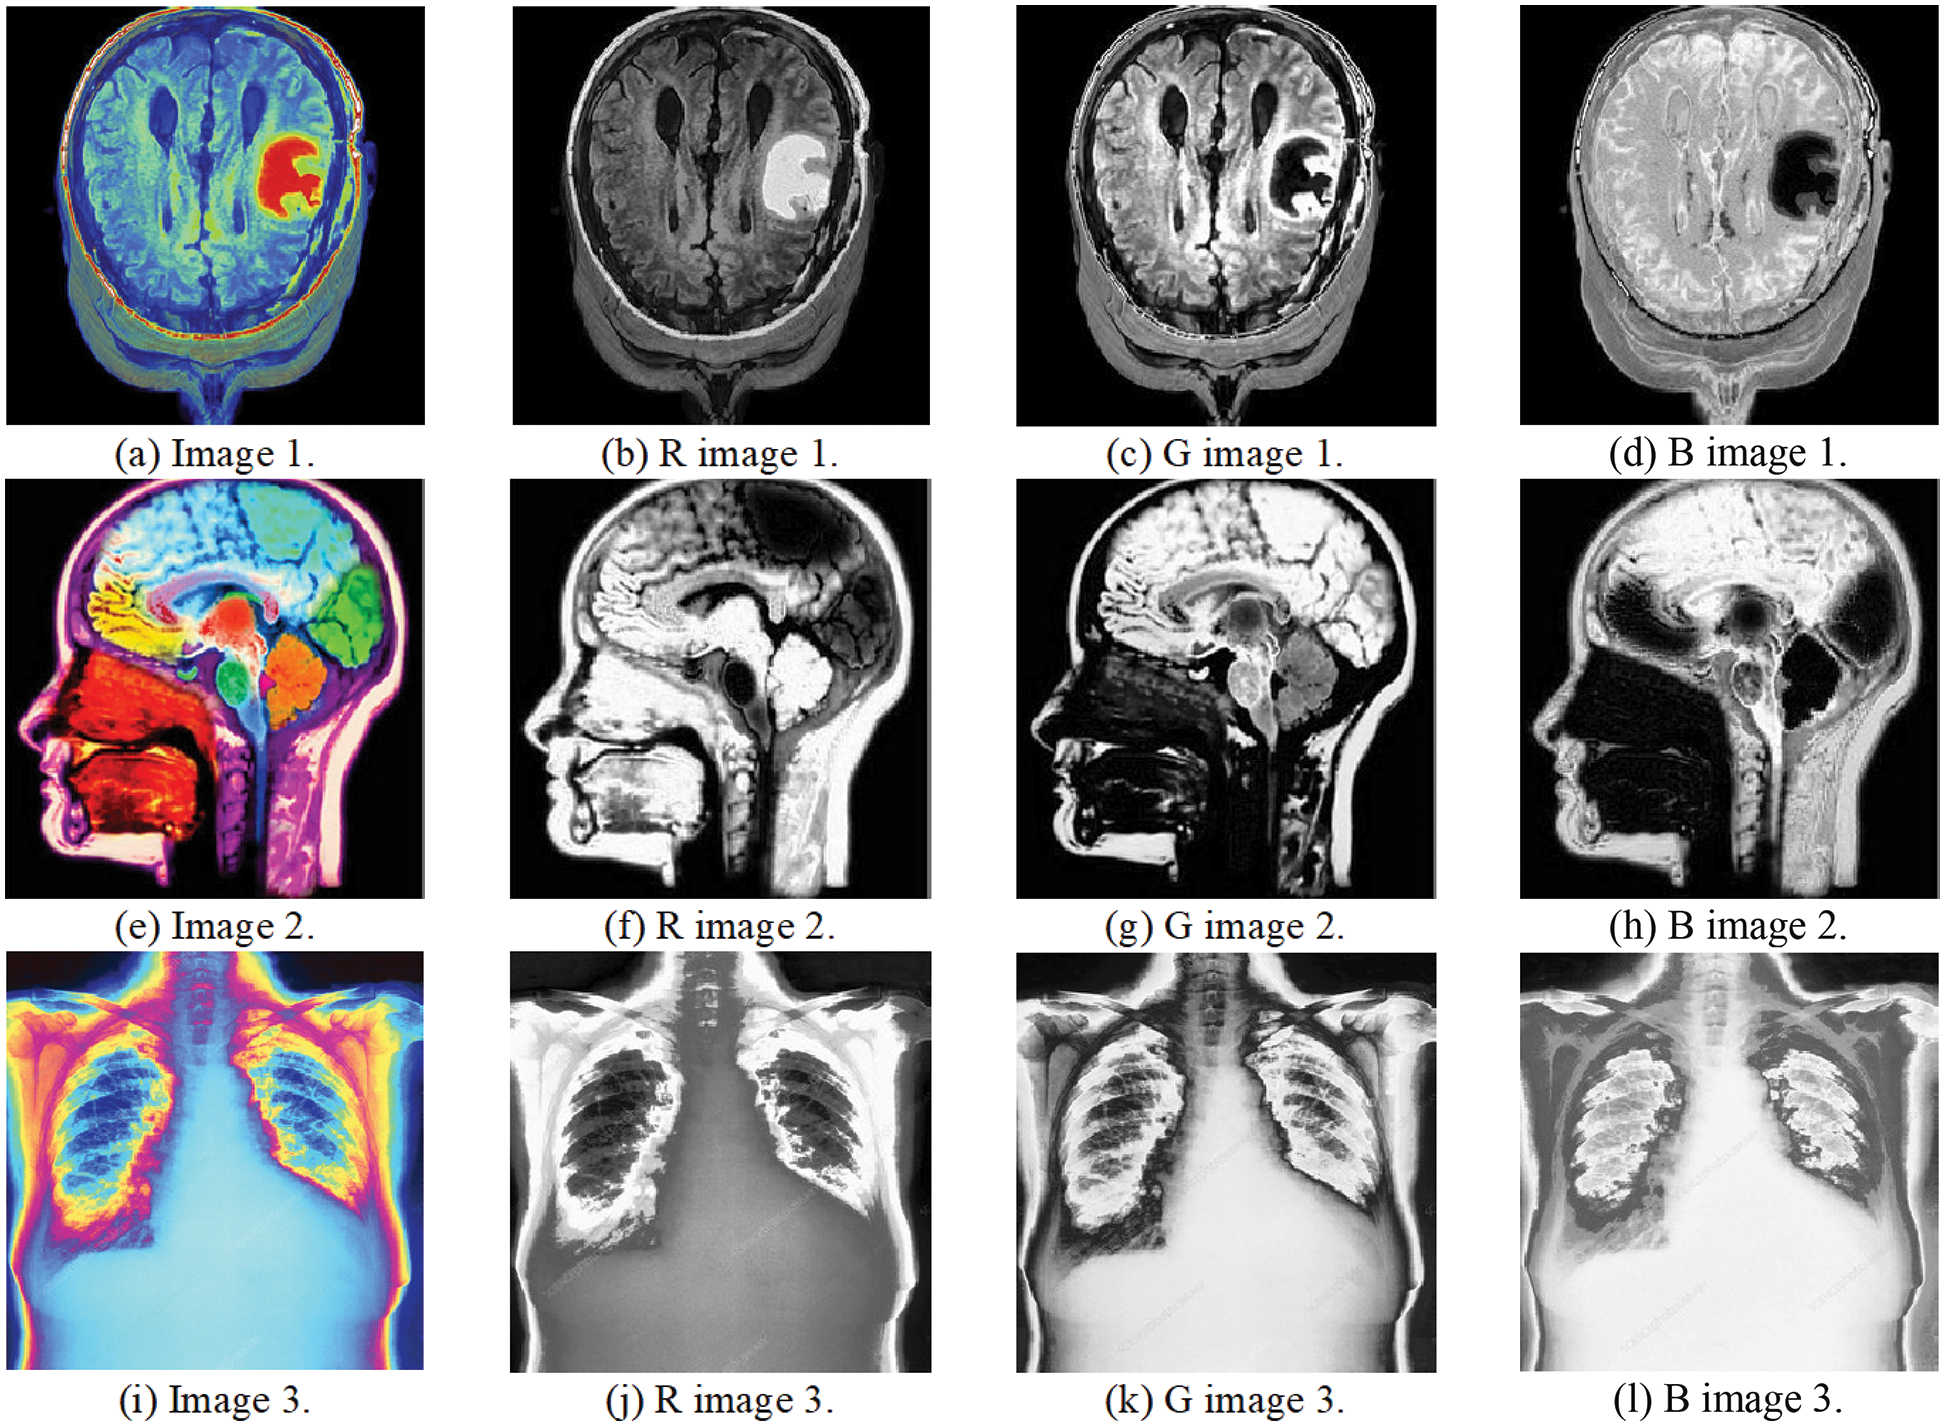

Simulation tests on three medical images have been carried out to evaluate the presented multi-stage security solution. The subjective results guarantee watermark indiscernibility and no retrogression in the watermarked color medical image quality in contrast to the host images. The CC values of the extracted distorted watermarks and the PSNR values of the watermarked images were calculated. Various multimedia attacks were implemented and tested in the simulation experiments on the watermarked medical images. Then, the watermarks were extracted to assess the strength of the proposed security algorithm. Different simulation experiments were conducted on three host medical images. Fig. 7 shows the three host medical images and their RGB elements. All these plaintext medical images are collected from (https://openmd.com/) and (https://medpix.nlm.nih.gov). Fig. 8 presents the color watermarks and their RGB elements, whereas Fig. 9 shows the gray watermarks.

Figure 7: Medical images and their RGB elements